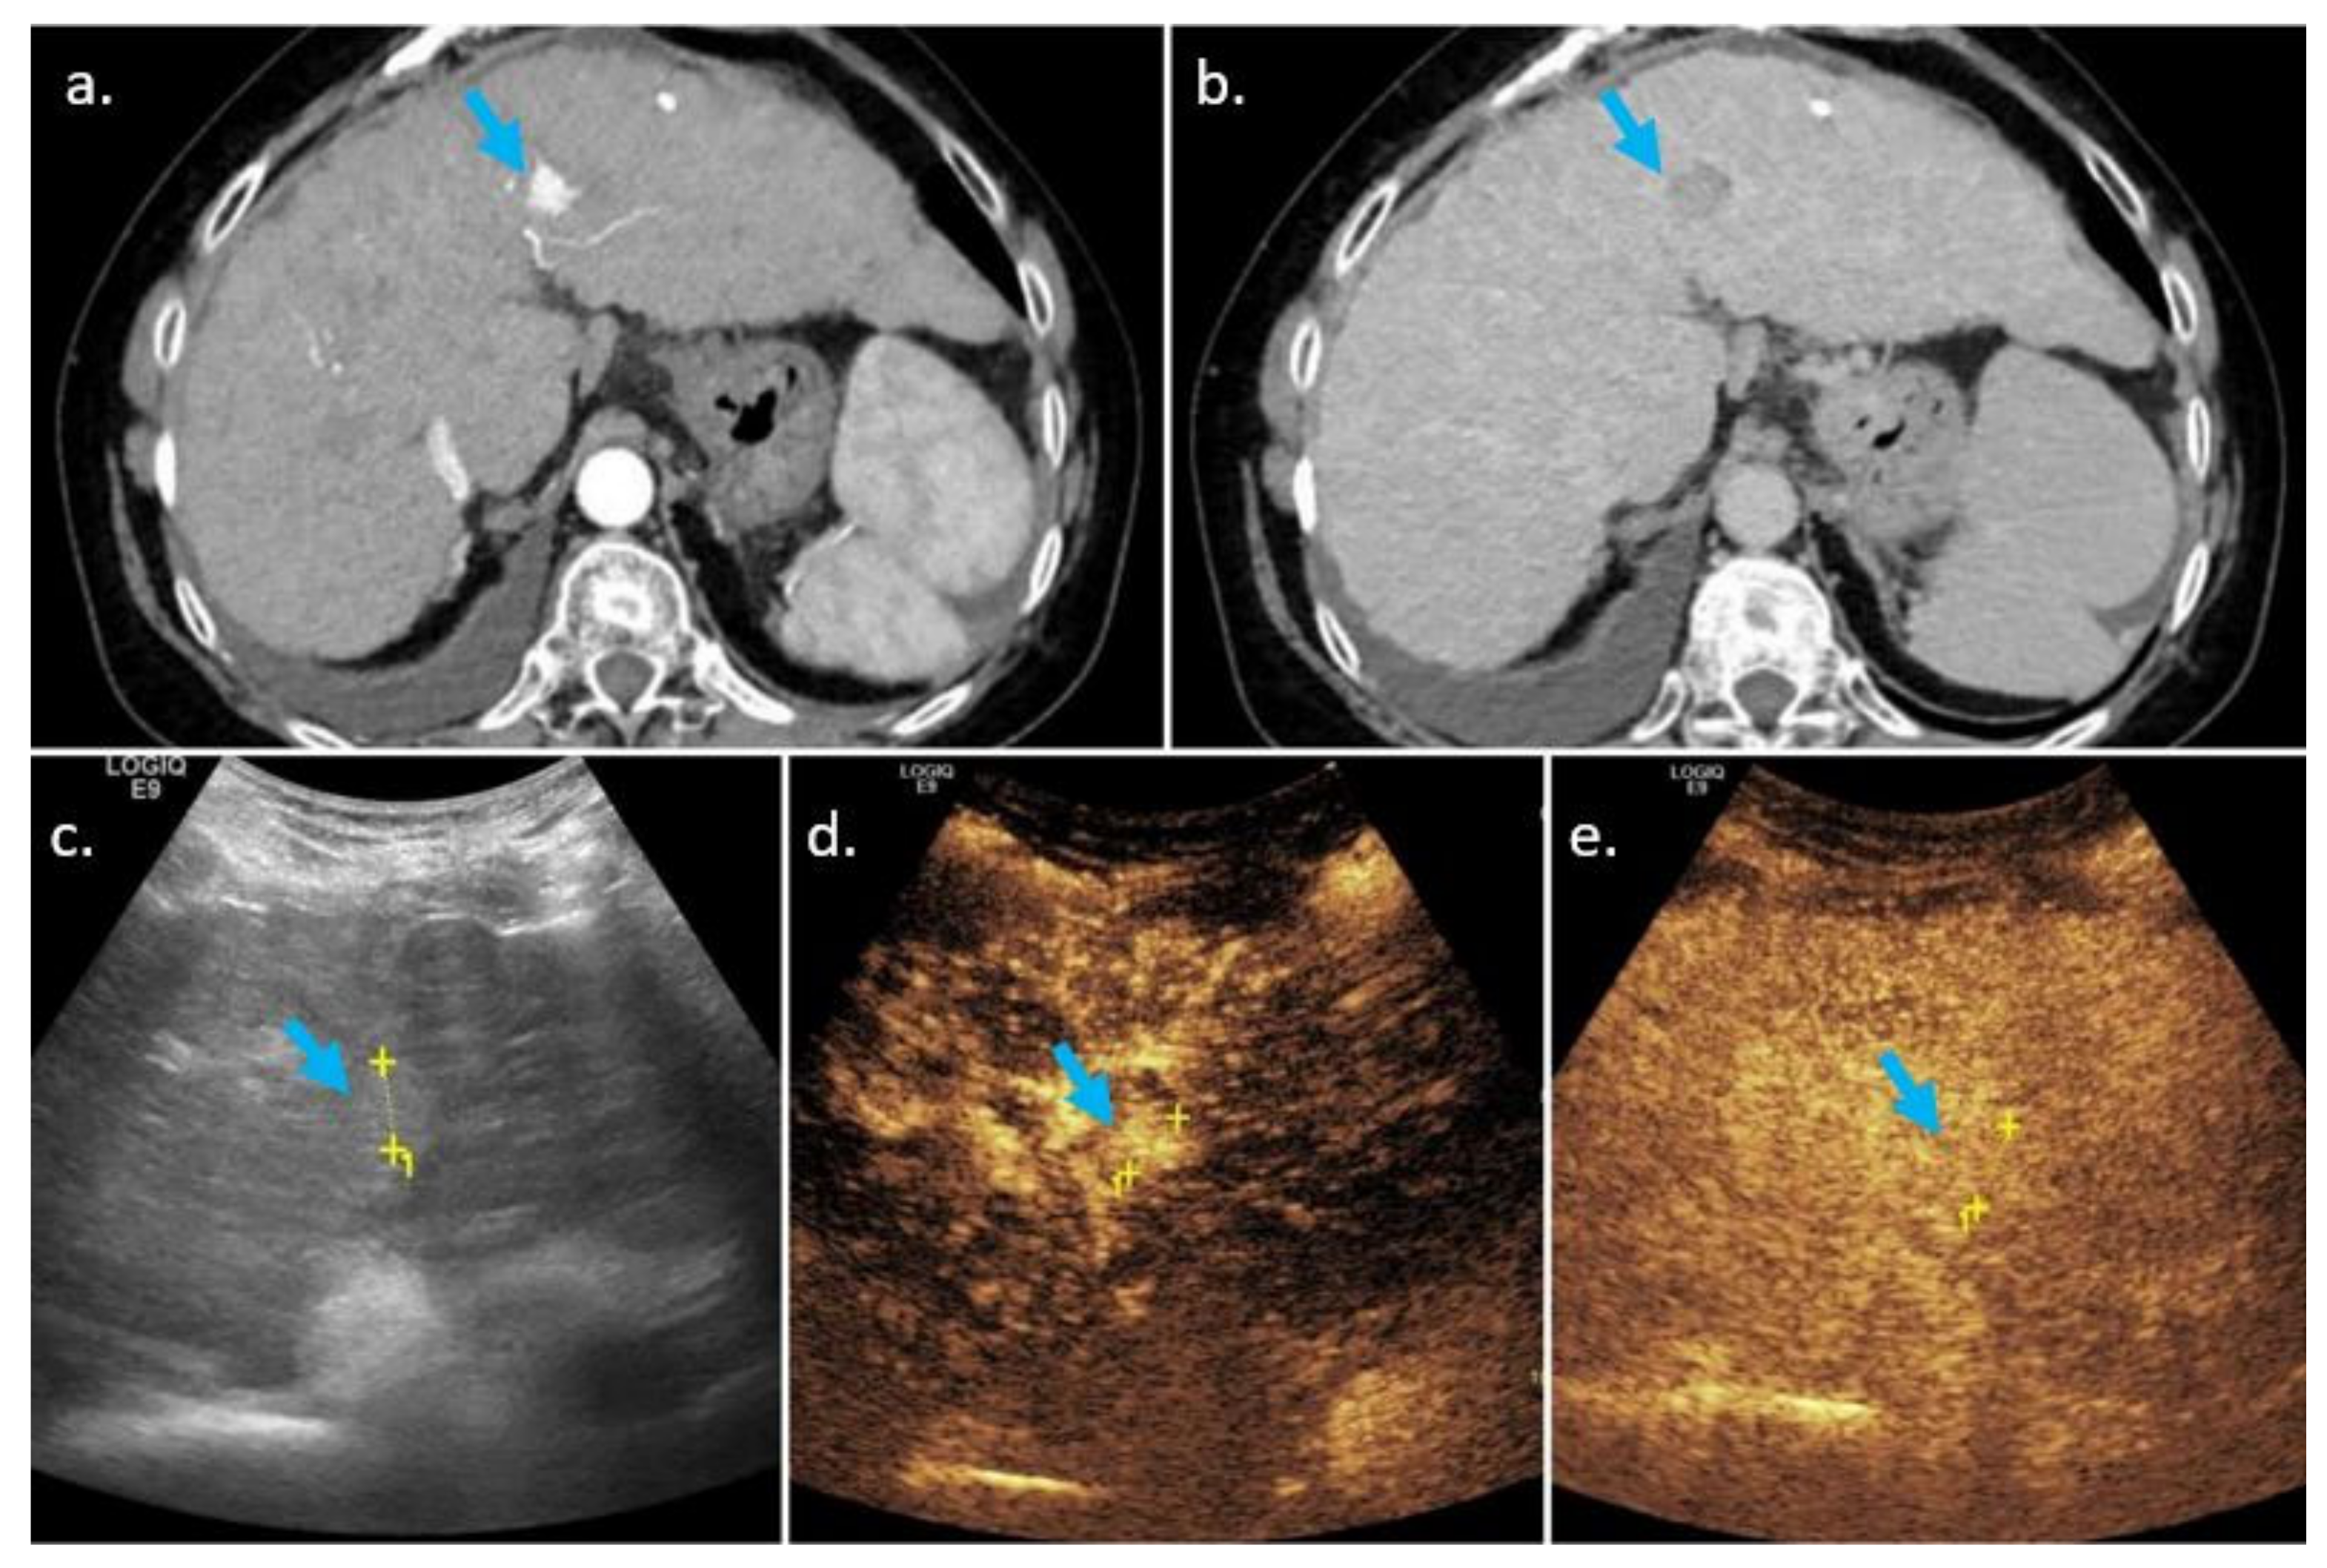

3.3. Threshold Growth

3.3.1. Definition

3.3.2. Comparison of CEUS, CECT, and MRI, Similarities and Differences

Similarities

Differences and Complementarity of Techniques

- Threshold growth is a major feature for HCC in the CT/MRI LI-RADS core document, but only an ancillary feature suggesting malignancy in the CEUS core document.

- Definite growth is defined by the CEUS LI-RADS core document as the unequivocal increase in size of a lesion; there is no established “threshold”, but >5 mm is generally considered unequivocal growth. Ultrasound should only be compared with ultrasound and the size increase should not be attributable to artifacts, measurement errors, or difference in technique [46].

- Unequivocal growth evaluated by CEUS favors malignancy in general, not HCC in particular (as threshold growth does in CT/MRI).

- Using the arterial phase of enhancement when measuring an observation should be avoided, if possible, on CT/MRI due to the risk of overestimating the lesion size. On CEUS, measuring the observation can, in most cases, only been done in the arterial phase. On CT/MRI, an observation should be measured in the phase, sequence, and plane in which its margins are the most clear. In the meantime, measuring a lesion in the arterial phase or on diffusion weighted imaging should be avoided [47].

- Threshold growth is considered of less importance in CEUS as compared to CT/MRI. This is because of the lesser reproducibility of US images as compared to CT/MRI and the difficulties of obtaining the same plane of the lesion on seriate US examinations [6].

- Increase in size of a lesion is a criterion with good specificity for the diagnosis of HCC [48]. Threshold growth on CT/MRI is defined by an increase in size of one nodule of more than 50% over less than 6 months; however, any increase in size of a nodule is considered an ancillary feature on CEUS examination [4]. Therefore, we recommend associating CT or MRI in every patient for whom US/CEUS suggests increase in size of a nodule—unequivocal threshold growth associated with APHE can classify the nodule as LI-RADS 5 and biopsy can be avoided.